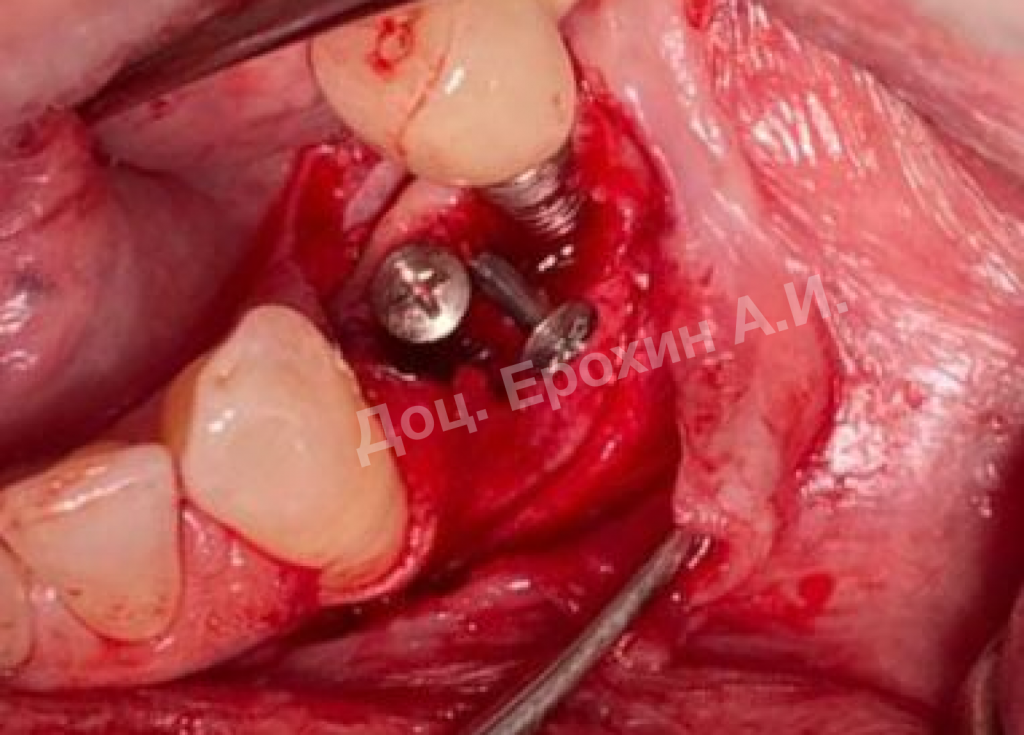

Вертикальные аугментации — самый непредсказуемый тип костной пластики методом НРТ. Мембрана способна коллапсировать, смещая в апикальном направлении костный материал, тем самым полностью нивелирую потраченные усилия.

Тентовые винты имеют широкие шляпки, которые позволяют мембране опираться на них, тем самым препятствуя изменению профиля регенерируемого участка.